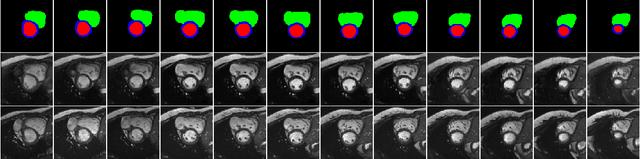

Abstract:Generative adversarial networks (GANs) have provided promising data enrichment solutions by synthesizing high-fidelity images. However, generating large sets of labeled images with new anatomical variations remains unexplored. We propose a novel method for synthesizing cardiac magnetic resonance (CMR) images on a population of virtual subjects with a large anatomical variation, introduced using the 4D eXtended Cardiac and Torso (XCAT) computerized human phantom. We investigate two conditional image synthesis approaches grounded on a semantically-consistent mask-guided image generation technique: 4-class and 8-class XCAT-GANs. The 4-class technique relies on only the annotations of the heart; while the 8-class technique employs a predicted multi-tissue label map of the heart-surrounding organs and provides better guidance for our conditional image synthesis. For both techniques, we train our conditional XCAT-GAN with real images paired with corresponding labels and subsequently at the inference time, we substitute the labels with the XCAT derived ones. Therefore, the trained network accurately transfers the tissue-specific textures to the new label maps. By creating 33 virtual subjects of synthetic CMR images at the end-diastolic and end-systolic phases, we evaluate the usefulness of such data in the downstream cardiac cavity segmentation task under different augmentation strategies. Results demonstrate that even with only 20% of real images (40 volumes) seen during training, segmentation performance is retained with the addition of synthetic CMR images. Moreover, the improvement in utilizing synthetic images for augmenting the real data is evident through the reduction of Hausdorff distance up to 28% and an increase in the Dice score up to 5%, indicating a higher similarity to the ground truth in all dimensions.

Abstract:We propose a hybrid controllable image generation method to synthesize anatomically meaningful 3D+t labeled Cardiac Magnetic Resonance (CMR) images. Our hybrid method takes the mechanistic 4D eXtended CArdiac Torso (XCAT) heart model as the anatomical ground truth and synthesizes CMR images via a data-driven Generative Adversarial Network (GAN). We employ the state-of-the-art SPatially Adaptive De-normalization (SPADE) technique for conditional image synthesis to preserve the semantic spatial information of ground truth anatomy. Using the parameterized motion model of the XCAT heart, we generate labels for 25 time frames of the heart for one cardiac cycle at 18 locations for the short axis view. Subsequently, realistic images are generated from these labels, with modality-specific features that are learned from real CMR image data. We demonstrate that style transfer from another cardiac image can be accomplished by using a style encoder network. Due to the flexibility of XCAT in creating new heart models, this approach can result in a realistic virtual population to address different challenges the medical image analysis research community is facing such as expensive data collection. Our proposed method has a great potential to synthesize 4D controllable CMR images with annotations and adaptable styles to be used in various supervised multi-site, multi-vendor applications in medical image analysis.